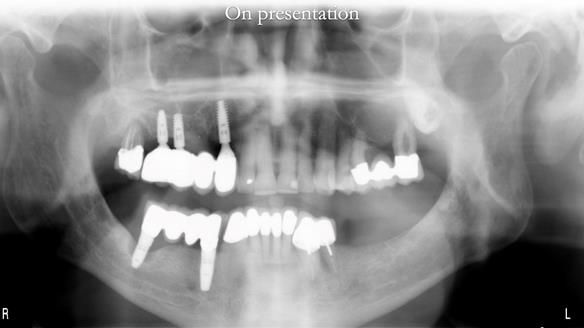

Like an increasing number of patients I now see (around 35% of referrals), Ken had implants that were failing or had already failed.

The starting point

We began with the lower jaw.

A posterior implant 47 had lost integration and was infected. This was removed.

Ken did not want further implant surgery.

Instead, we made a Scandinavian-style, metal-based lower RPD.